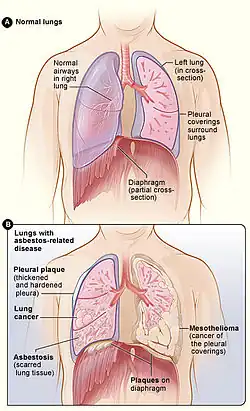

All types of asbestos fibers are known to cause serious health hazards in humans.[1][2][3] The most common diseases associated with chronic exposure to asbestos are asbestosis and mesothelioma.[4]

The most common diseases associated with chronic exposure to asbestos are asbestosis and mesothelioma.[4]

- Asbestosis: Progressive fibrosis of the lungs of varying severity, progressing to bilateral fibrosis, honeycombing of the lungs on radiological view with symptoms including rales and wheezing. Individuals who have been exposed to asbestos via home, environment, or work should notify their doctors about exposure history.

- Pleural plaques: discrete fibrous or partially calcified thickened area which can be seen on X-rays of individuals exposed to asbestos. Although pleural plaques are themselves asymptomatic, in some patients this develops into pleural thickening.

- Diffuse pleural thickening: similar to above and can sometimes be associated with asbestosis. Usually no symptoms shown but if exposure is extensive, it can cause lung impairment.

- Malignant mesothelioma: an aggressive and incurable tumour arising from mesothelial cells of the pleura (the lining of the thoracic cavity).